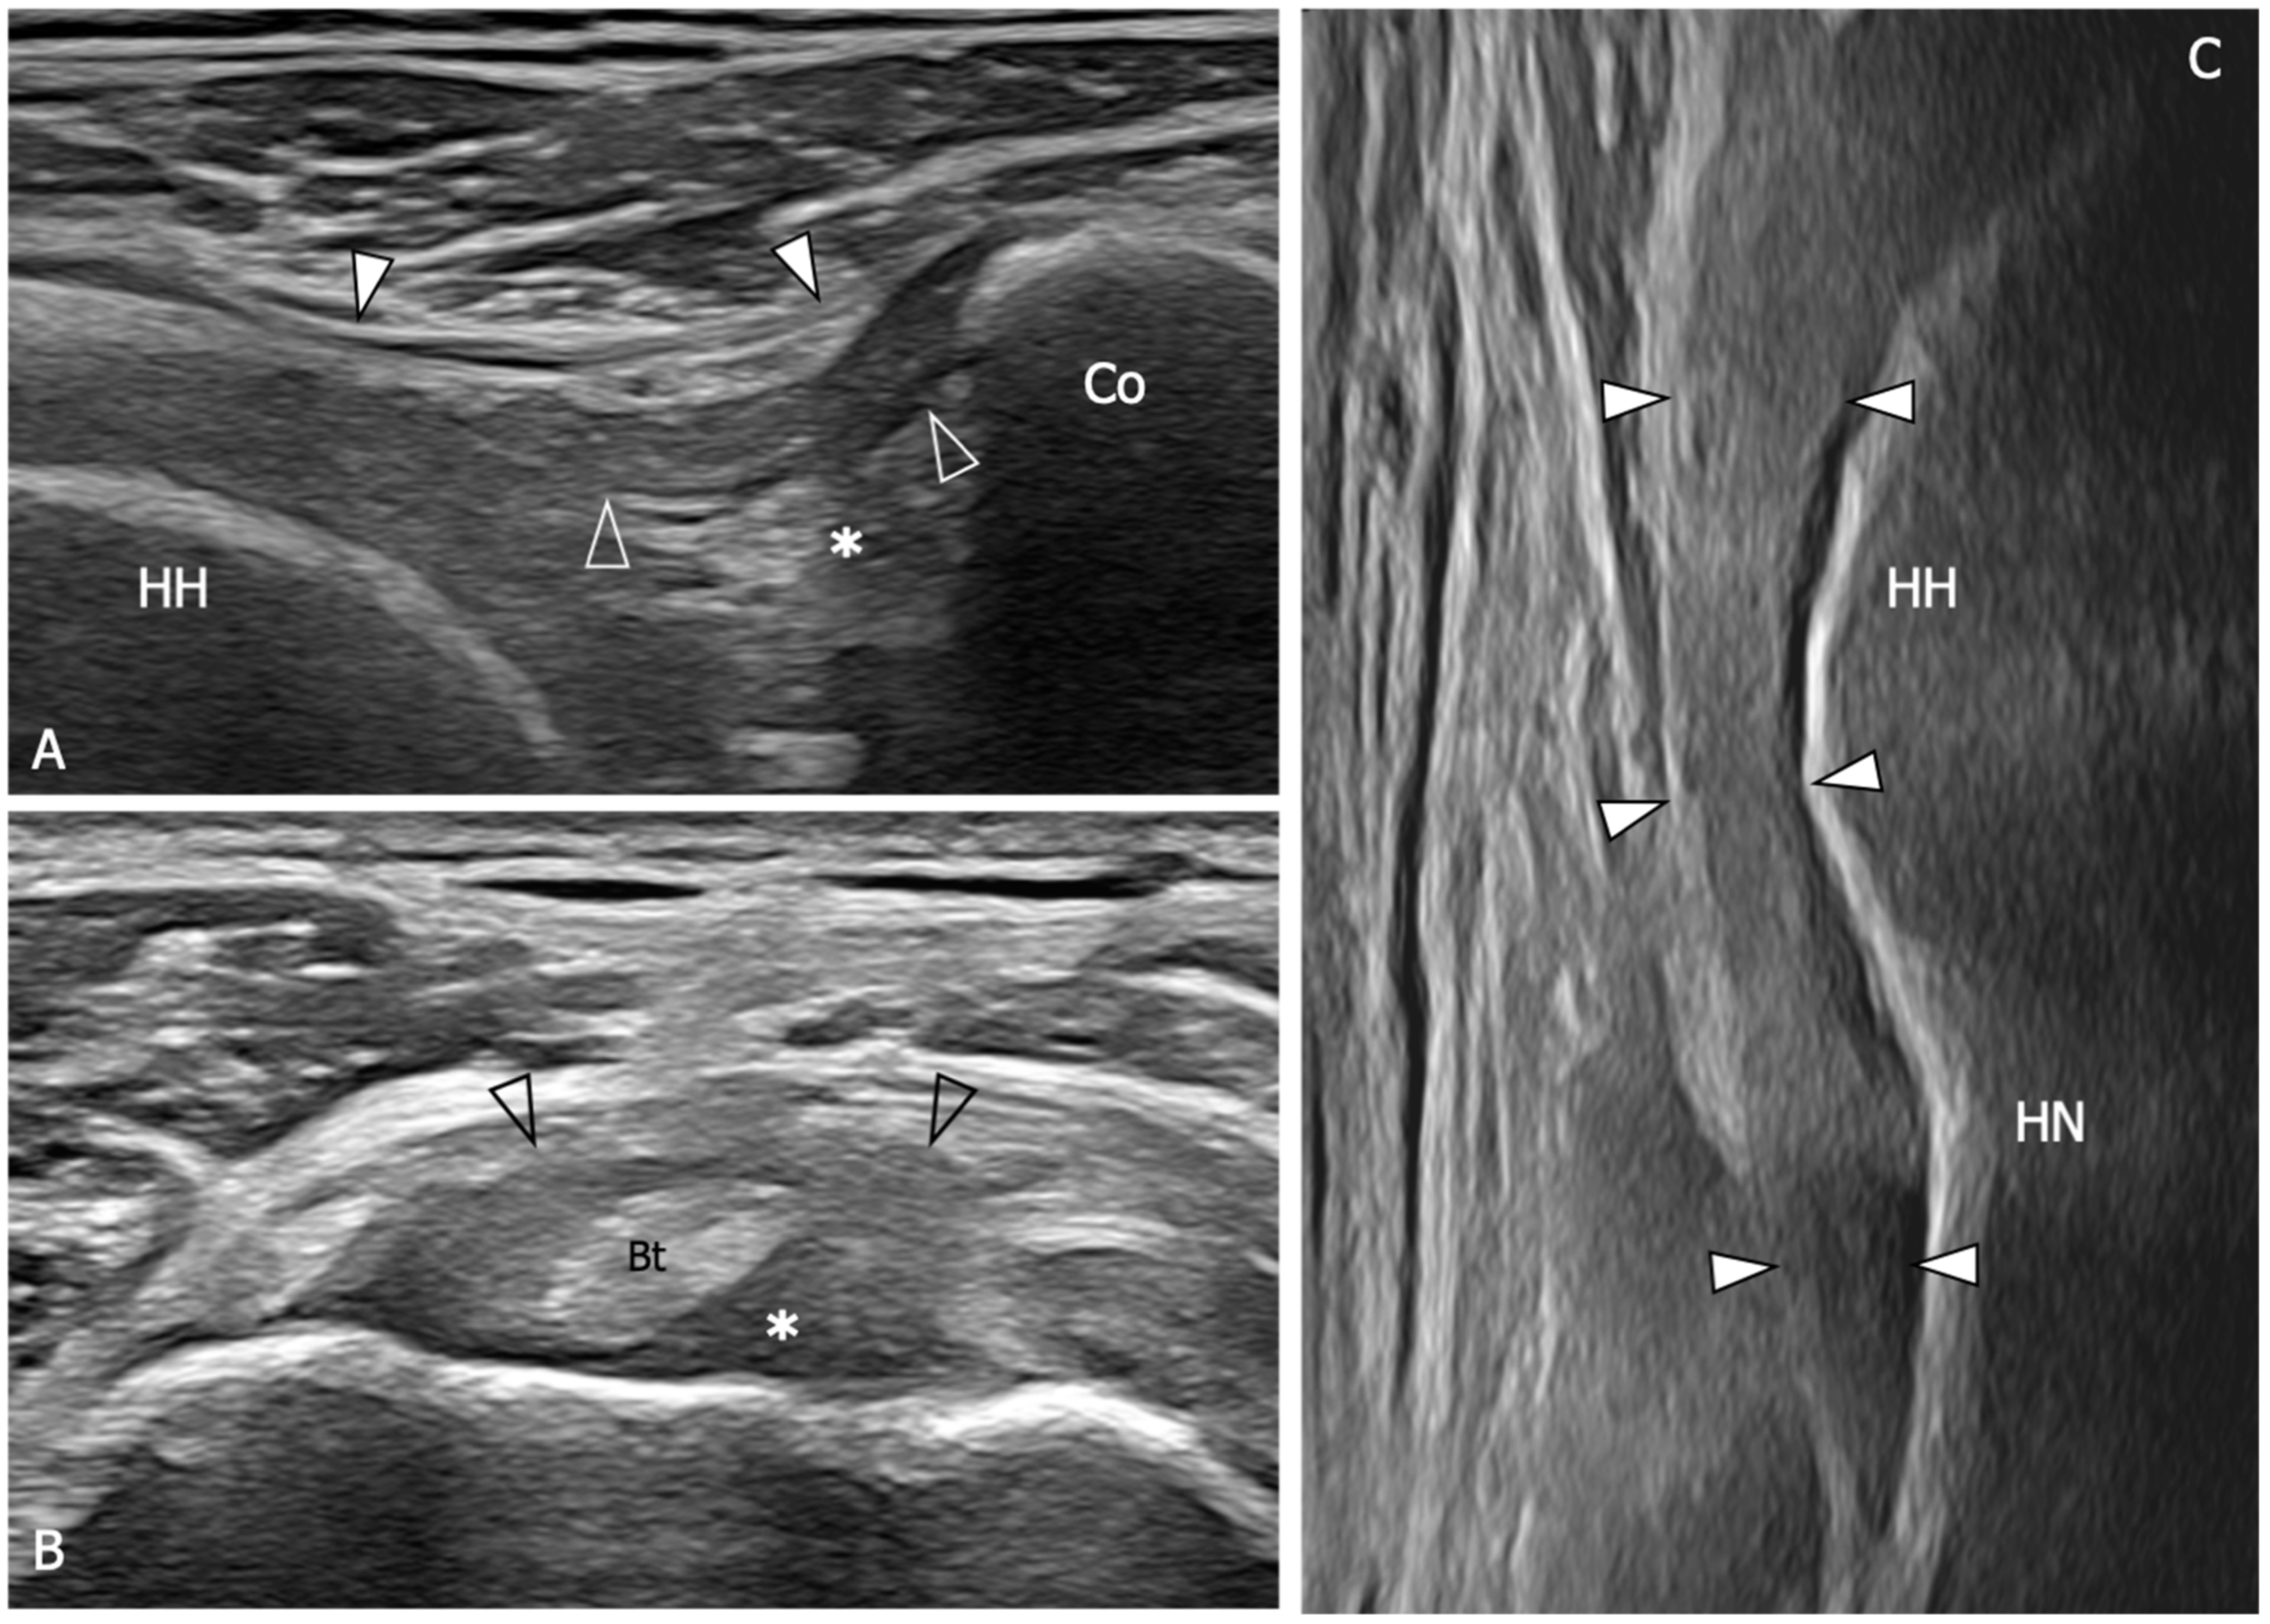

Figure 5.

Glenohumeral joint capsule and pericapsular ligaments, normal US findings. (A) Oblique transverse 18–5 MHz US image shows the normal thin and fibrillar appearance of the coracohumeral ligament (outlined arrowheads), which is demonstrated connecting the coracoid (Co) and humeral head (HH) in a deeper position respective to the coracoacromial ligament (arrowheads). Note the homogeneous and hyperechoic appearance of the subcoracoid fat (asterisk). (B) Short-axis 18–5 MHz US image shows the distal part of the coracohumeral ligament (outlined arrowheads) in the area of the rotator interval and the biceps pulley (asterisk). Bt, long head of the biceps tendon. (C) Longitudinal 18–5 MHz US obtained orienting the probe parallel to the humerus in the axillary region shows the inferior capsule (arrowheads) overlying the humeral head (HH) and folding over the humeral neck (HN).

Figure 6.

US findings in a 53 year old woman with adhesive capsulitis. (A) Oblique transverse 18–5 MHz US image demonstrates the markedly thickened coracohumeral ligament (outlined arrowheads), which has lost the normal fibrillar echotexture and appears homogeneously hypoechoic due to fibrotic changes and degeneration of the fibers. Note the presence of hypoechoic synovial tissue in the subcoracoid triangle (asterisk). Arrowheads, coracoacromial ligament. (B) Short-axis 18–5 Mhz US evidences the thickening and fibrotization of the coracohumeral ligament (arrowheads) and the biceps pulley (asterisks) in the rotator interval. (C) Longitudinal 18–5 MHz US image shows a significant thickening of the inferior capsule (arrowheads). HH, humeral head; Co, coracoid; Bt, long head of the biceps tendon; HN, humeral neck.